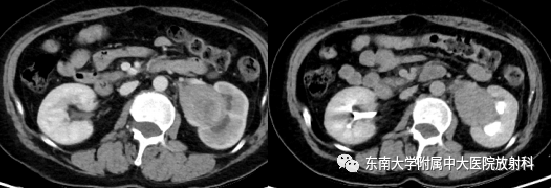

肾盂癌分型及其鉴别诊断

病例

女,52岁

主诉:肉眼血尿1年

现病史:患者无明显诱因下出现肉眼血尿,阵发左侧腰疼,无尿频尿急,于当地医院就诊查彩超结果无特殊,后多次复查影像学结果无特殊,症状无好转